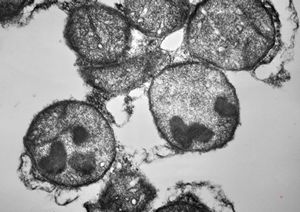

M,7m. | Birbeck granules (Langerhans granules, X-granules) - skin, histiocytosis X

M,7m. | Birbeck granules (Langerhans granules, X-granules) - skin, histiocytosis X

M,1y. | Birbeck granules (X-granules) - skin, histiocytosis X

M,1y. | Birbeck granule (X-granule) - skin, histiocytosis X